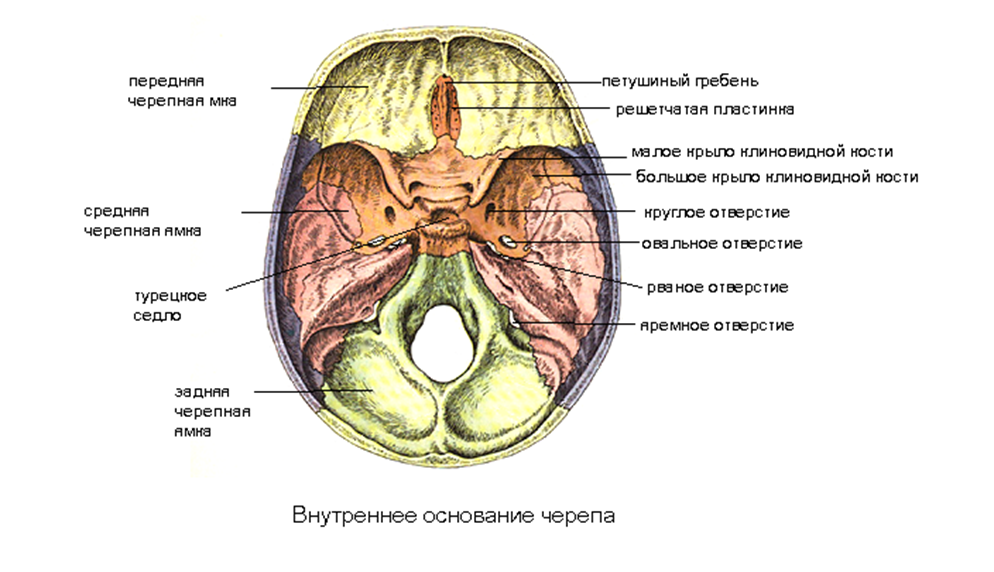

Необычные объекты: Переднее продырявленное вещество

Раздел: Альбом открытий